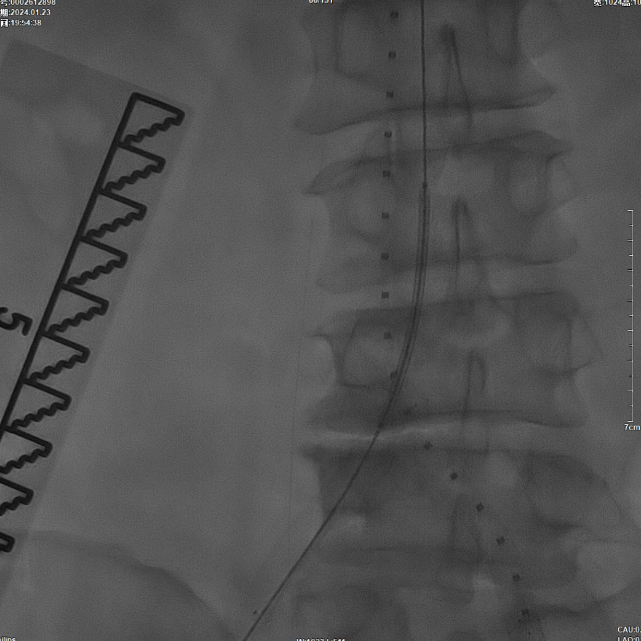

后扩张处理

首先使用14mm球囊进行初步扩张,鉴于腹主动脉直径约15mm,最终选用16mm球囊进行扩张。

当扩张压力达10 ATM时,患者出现轻微疼痛,遂停止扩张。扩张前需将左侧导丝撤出,扩张后重新置入并确认导丝位于支架内。